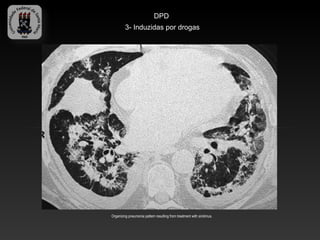

DPD

3- Induzidas por drogas

-Grande número drogas, tanto citotóxicas, quanto não citotóxicas podem

apresentar efeitos adversos nos pulmões.

-O diagnóstico requer correlação cuidadosa de exposição a droga,

achados clínicos e de imagem.

-Formas:

-   Lesão alveolar difusa

-   Pneumonia em organização

-   Pneumonia eosinofílica

-   PINE

-   Hemorragia pulmonar

-Bleomicina, amiodarona, metotrexate, sirolimus…

Organizing pneumonia pattern resulting from treatment with bleomycin.

Organizing pneumonia pattern resulting from treatment with sirolimus.